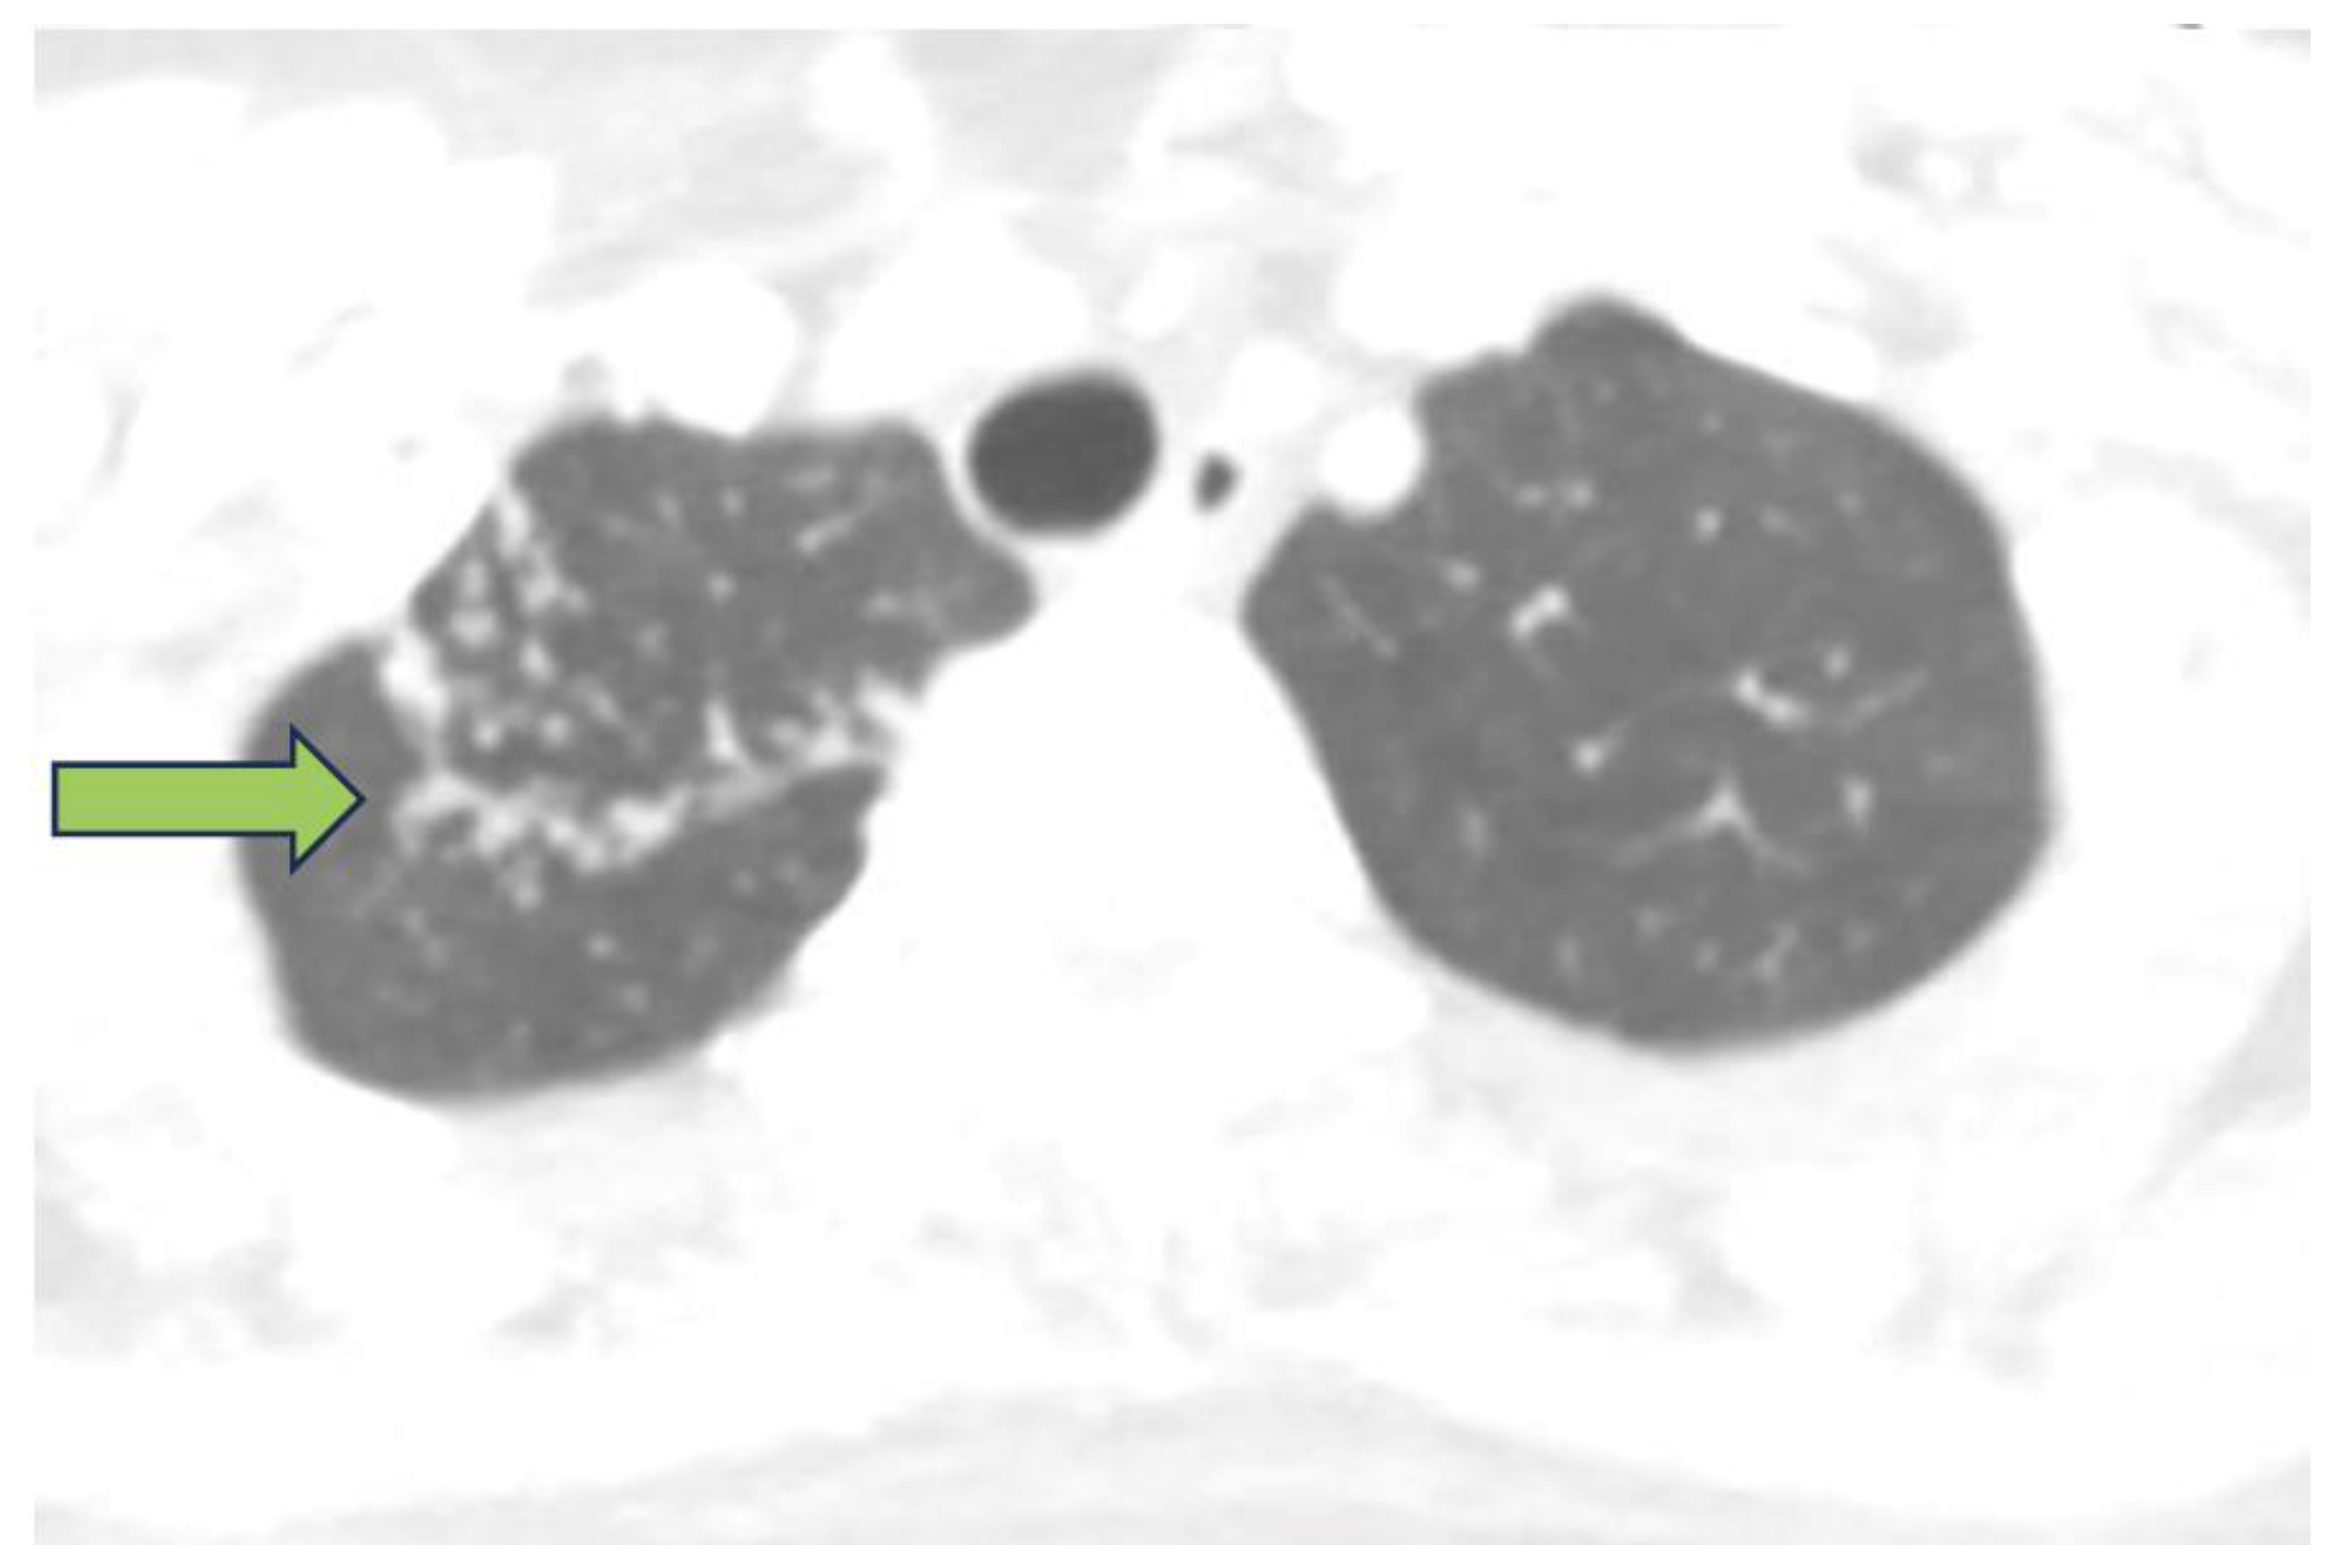

2. Detailed Case Presentation